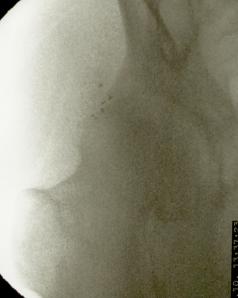

Más abajo se observarán unas imágenes de casos de implantes de oro en cadera